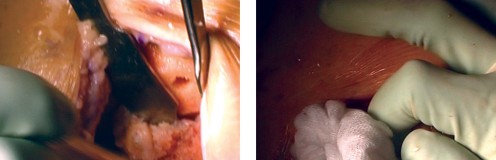

الخطوة 4: إكمال قطع عظم الفخذ وتحديد الحجم

- نظام التوجيه الخلفي: يُستخدم نظام توجيه خلفي لإكمال قطع عظم الفخذ.

- تحديد الدوران الخارجي: يُحدد المقدار الصحيح للدوران الخارجي لعظم الفخذ بناءً على المحور اللقمي الخلفي، والمحور فوق اللقمتين، وزاوية 90 درجة بالنسبة لمحور الساق (السطح المقطوع)، والمحور الأمامي الخلفي (خط وايتسايد).

- تحديد الحجم: يُوضع الدليل على الجزء البعيد من عظم الفخذ، ويُحدد حجم عظم الفخذ، ويُختار الحجم المطابق للمريض.